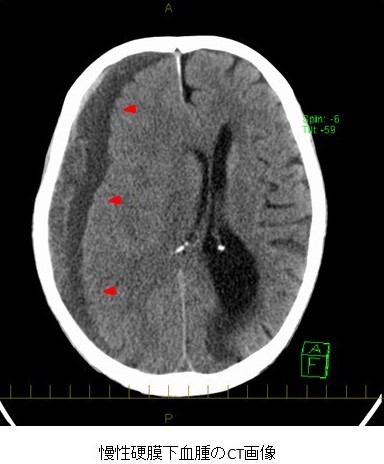

初発症状は頭痛が多く、続いて手足の麻痺や意識障害が認められます。特に高齢者では物忘れや性格変化などの認知障害や精神症状の出現で発見される場合があります。CTでは、前頭・頭頂・側頭部に三日月状に広がる血腫が認められ、正中偏位や脳室の圧排像などもみられます。無症状の場合には経過観察や内服加療による保存加療を行なうこともありますが、一般的には手術を行います。手術は、局所麻酔下に穿頭(頭蓋骨に直径1cmほどの穴をあける)を行い、液性の血腫のドレナージ(外に排出する)を行います。手術により症状は認知障害などを含め劇的に改善します。脳ヘルニアによる不可逆的脳損傷を起こした場合を除き、正しい診断のもとに時期を逸さず手術を行えば予後は極めて良好です。5〜10%の患者さんに血腫の再貯留を認め、再手術が必要となります。